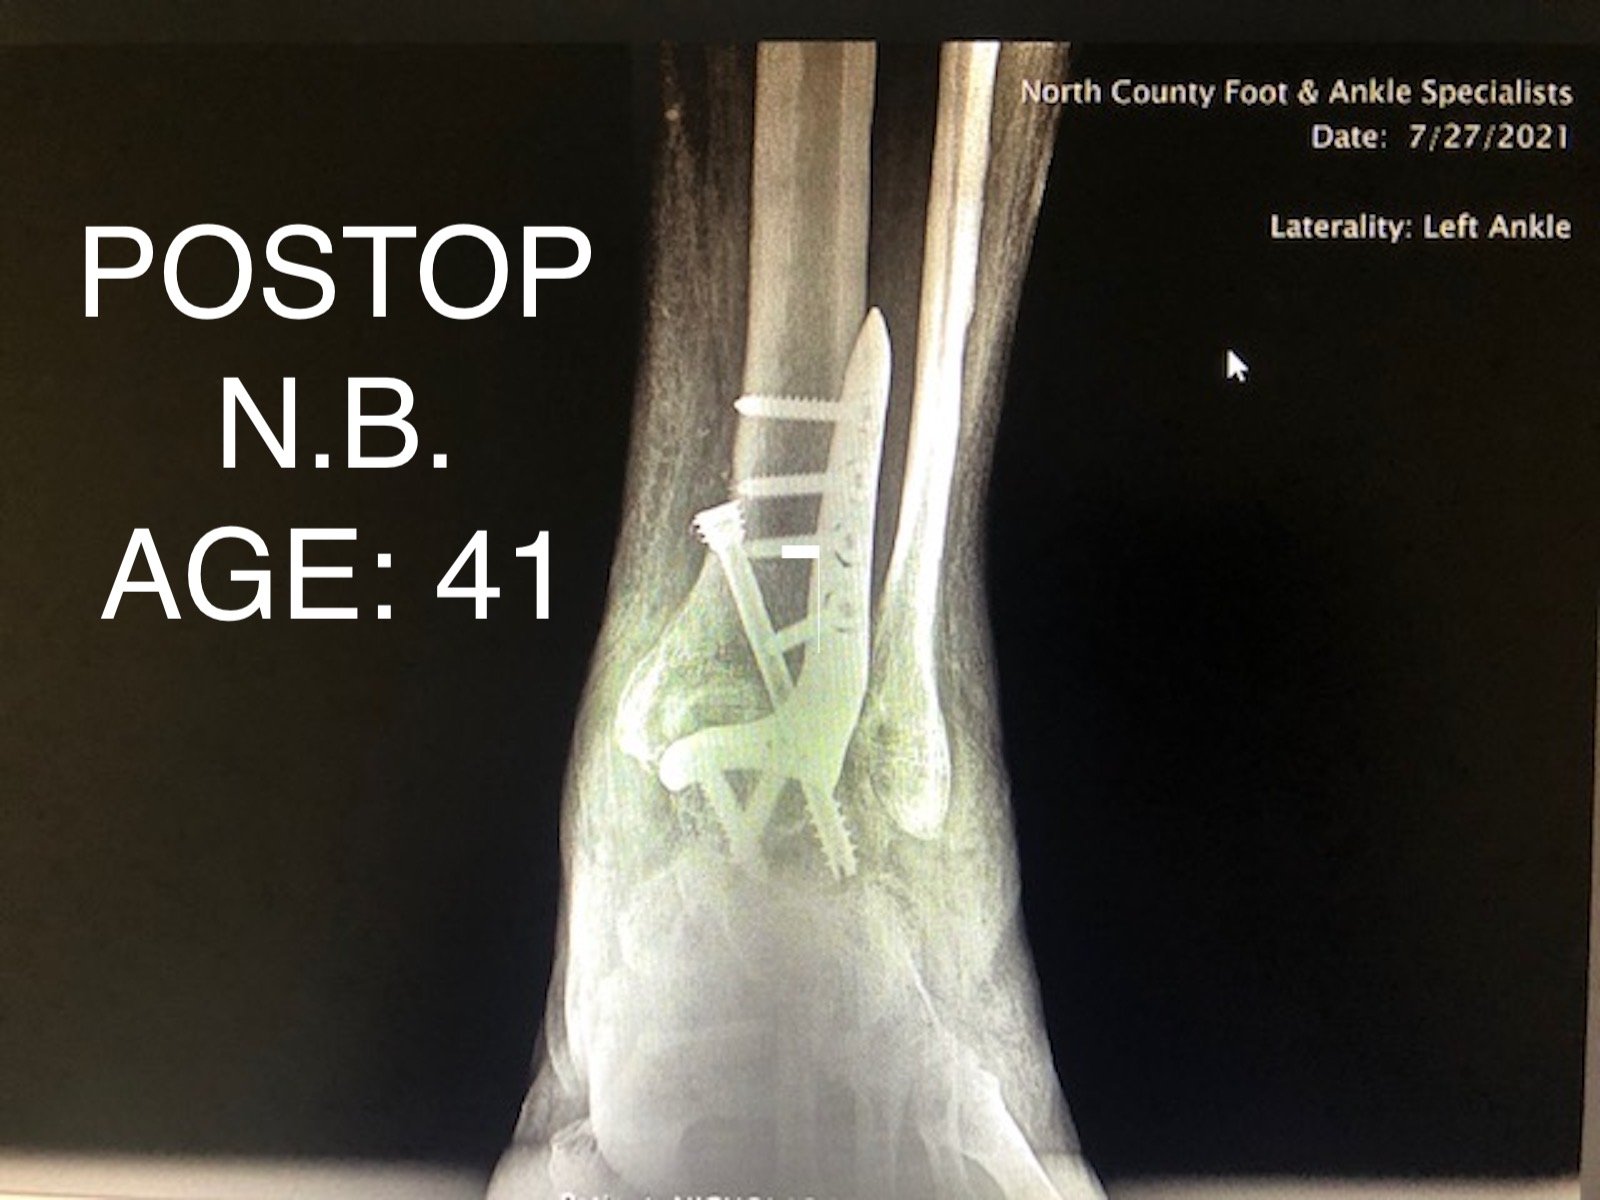

ANKLE FUSION